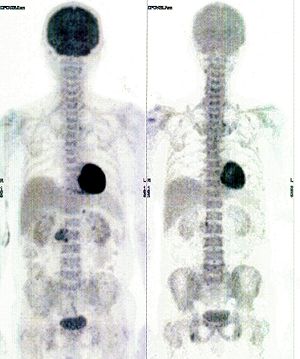

CASE NO: 10 (LUNG CANCER)

An old man with right lung cancer refused all cancer treatment, but was convinced to try our new cancer treatment because there is no severe side effect. After 3 treatment, the cancer shrunk to less than half the original size. He did not come back to continue the treatment.